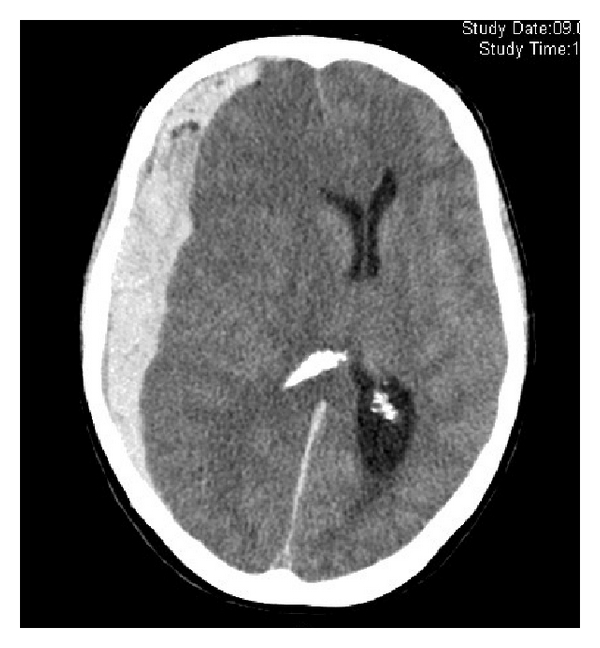

What type of bleed is this?

can the bleed cross suture lines?

subdural hematoma

yes, can cross suture lines